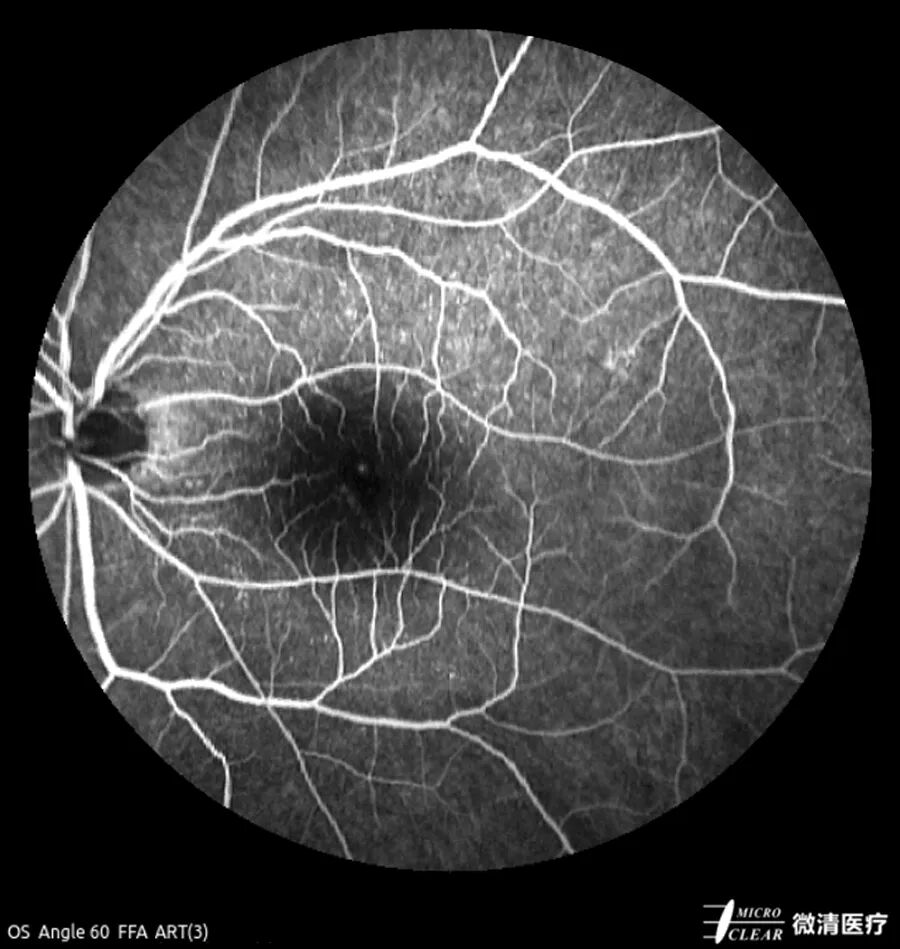

在分析解读造影影像时,通过多模式图像对比观察,可更全面、准确地判断病变性质。微清超广角激光眼底造影机支持彩照、自发荧光、荧光血管造影及同步造影等八种成像模式,可根据重点观察部位需要,一键切换四种不同拍摄角度,聚焦病灶,避免遗漏任何细节,并实现了单张165°超广角造影,全面观察累及周边部位疾病。